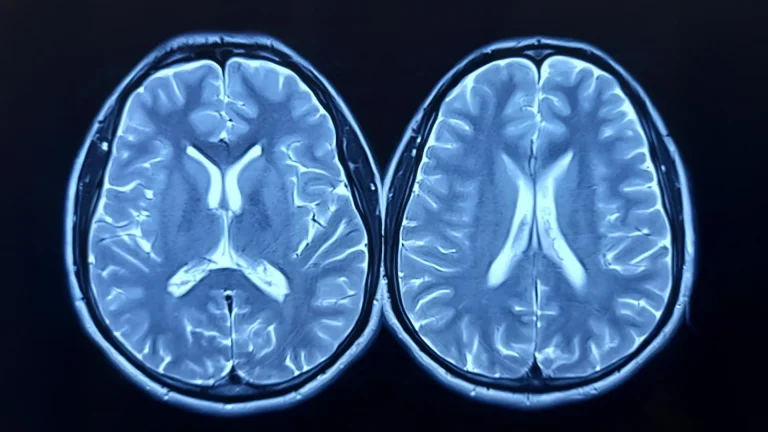

Scientists at Brown University have unveiled a novel method for detecting early indicators of Alzheimer’s disease, focusing...

An extensive, collaborative international scientific undertaking, leveraging advanced brain imaging techniques and comprehensive memory assessments from a...